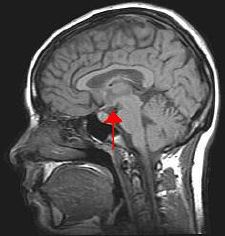

MRI of the human brain. The arrow indicates the position of the hypothalamus.

Biological psychology, also known as behavioral neuroscience, is the scientific study of the biological substrates of behavior and mental states. There are different specialties within behavioral neuroscience. For example, physiological psychologists use animal models, typically rats, to study the neural, genetic, and cellular mechanisms that underlie specific behaviors such as learning and memory and fear responses.[14] Cognitive neuroscientists investigate the neural correlates of psychological processes in humans using neural imaging tools, and neuropsychologists conduct psychological assessments to determine, for instance, specific aspects and extent of cognitive deficit caused by brain damage or disease.